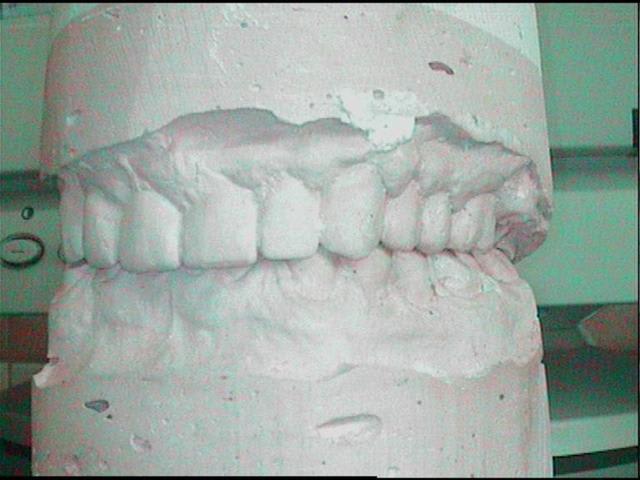

Modele initial m8gkxf - Eugenol